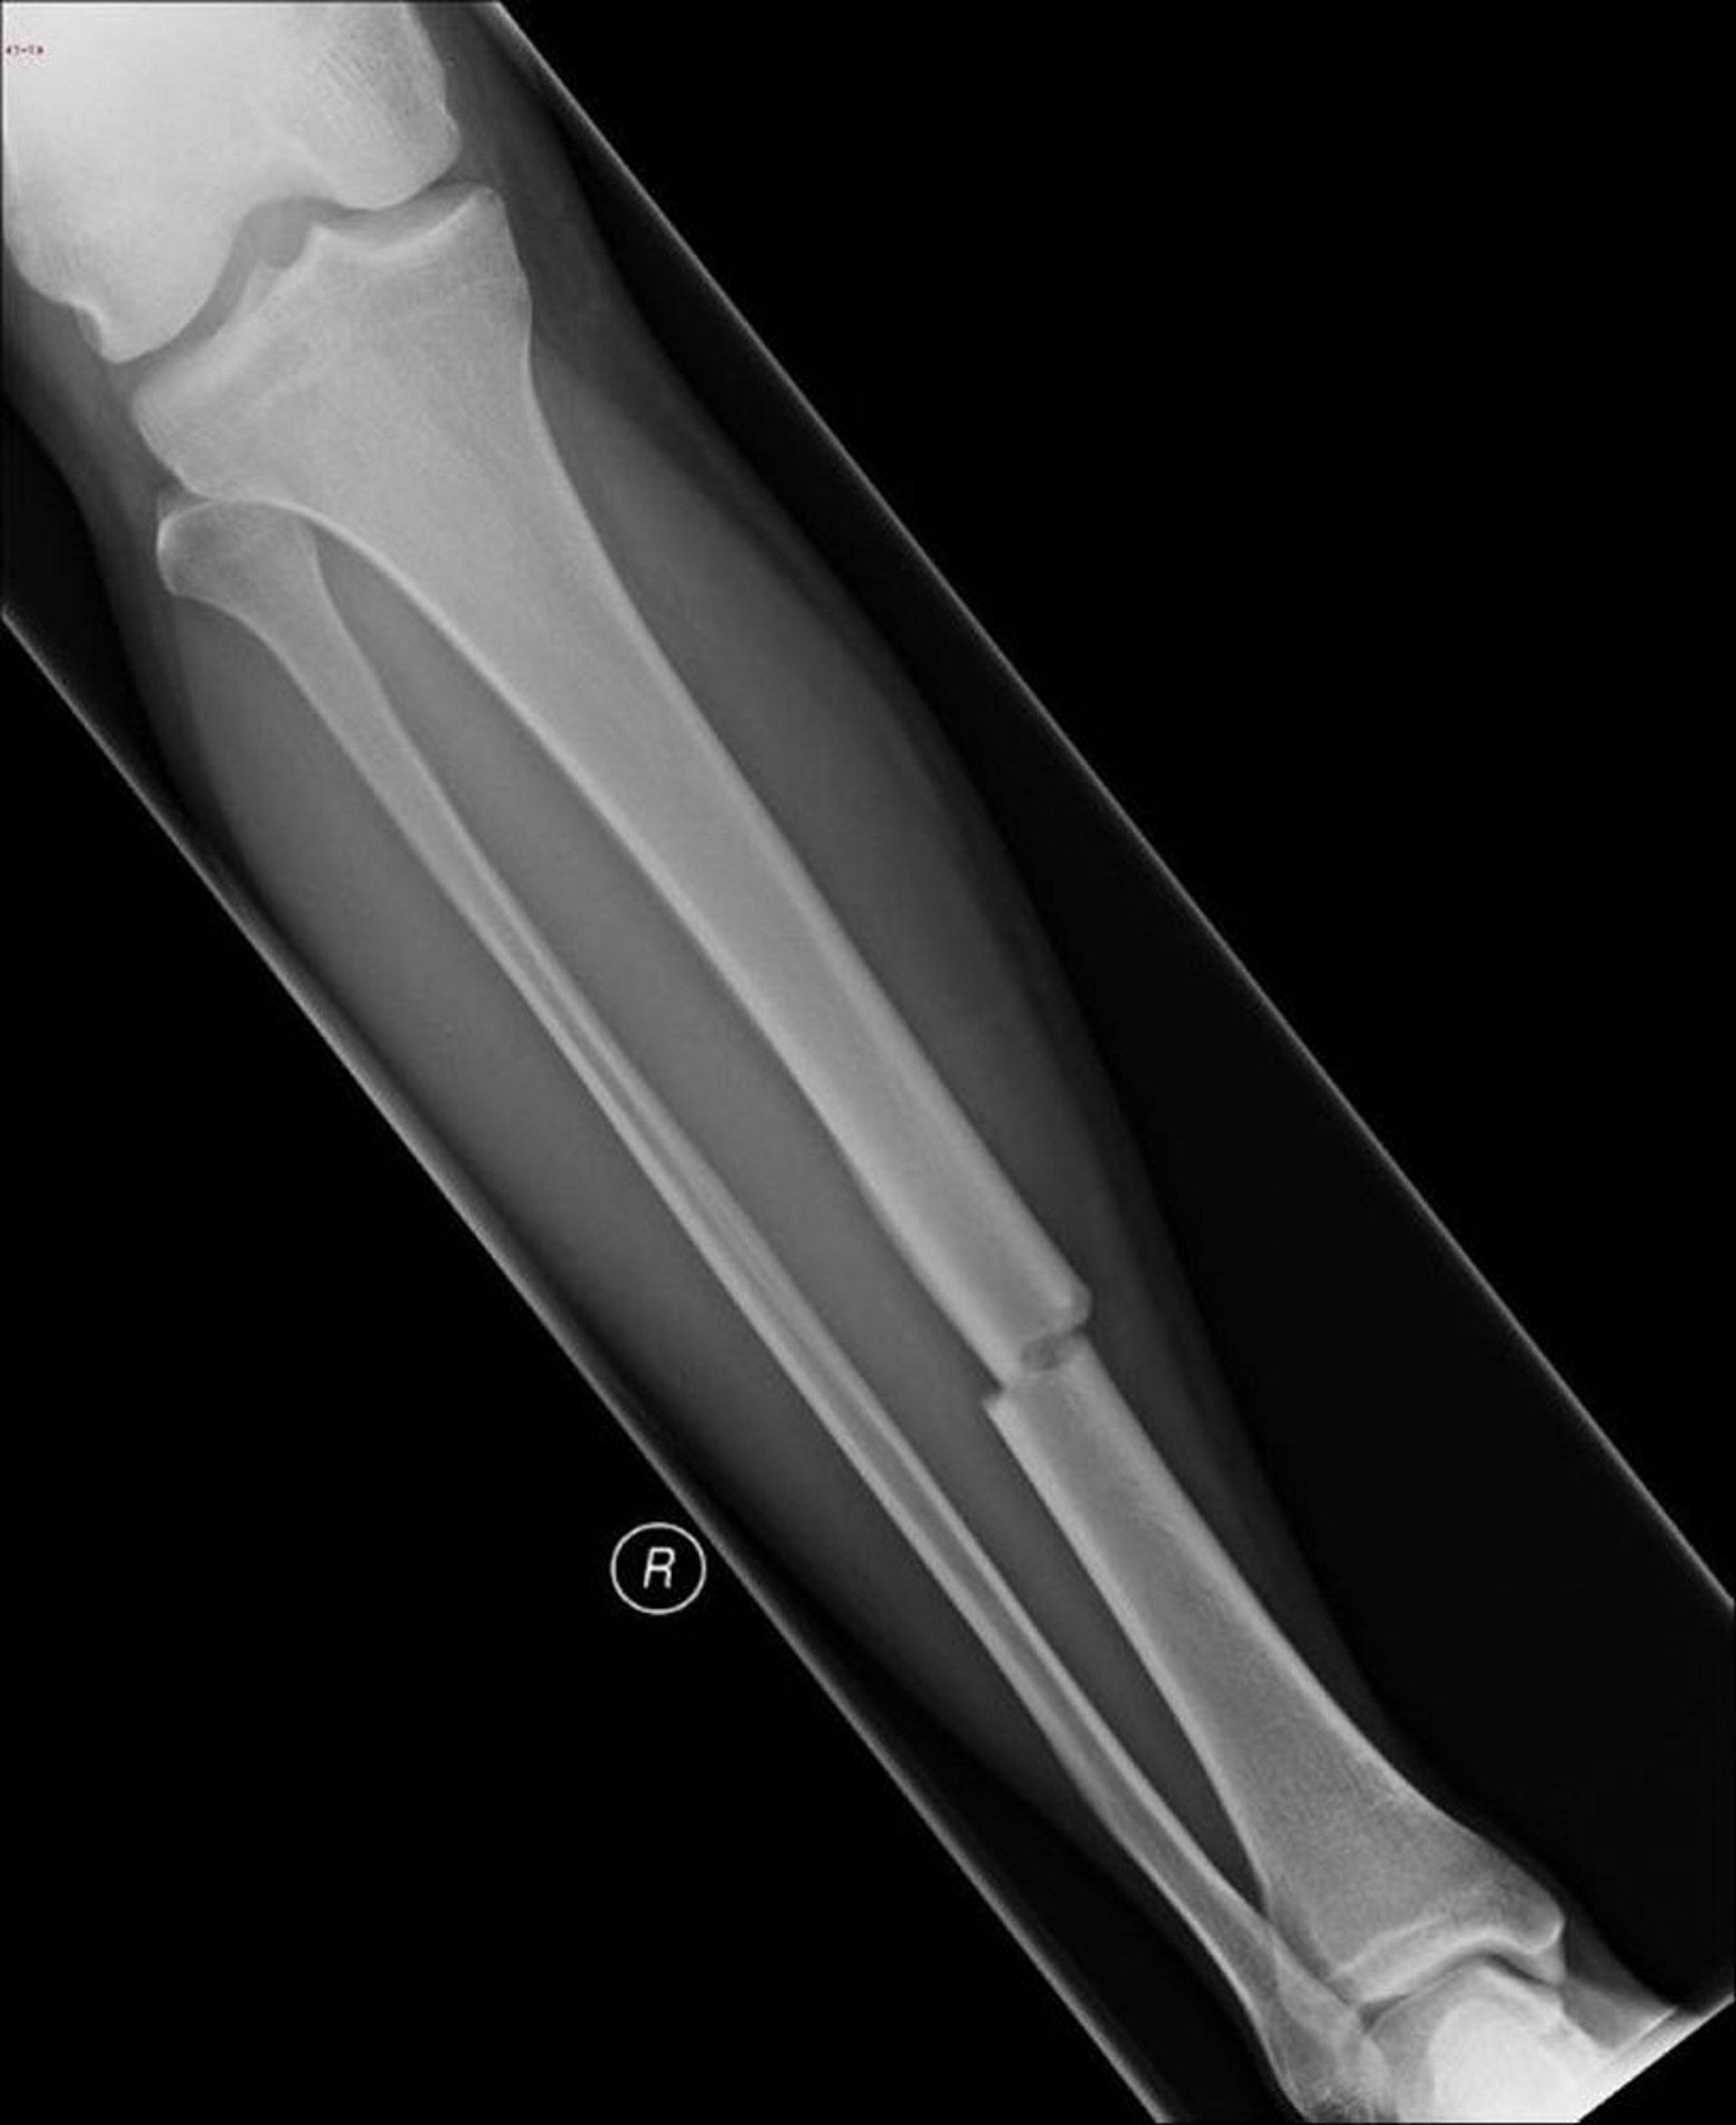

Esta imagen muestra un fémur fracturado en más de dos lugares (conminuta).

Imagen cortesía de Danielle Campagne, MD.